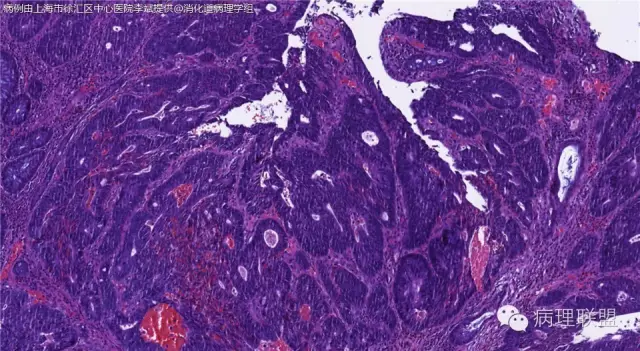

男,72岁,距肛门口30cm息肉。大体:灰白结节1.5*1*0.8cm拟发管状腺瘤并部分区高级别,请各位老师指导!(病例由上海市徐汇区中心医院 李斌 提供,致谢!)

这一例有两种不同看法,按WHO标准,为高级别,按实际工作,要发粘膜内癌。WHO第三版与第四版均提出,侵犯至粘膜下层才能诊断为癌,声称结直肠粘膜内没有淋巴管,发生转移的概率较小,但是粘膜内有血管,肿瘤侵出粘膜腺体基膜以外,就能侵犯血管,照样可以发生血道转移。文献报告与我们的工作实践,发现腺瘤、高级别(没有侵出基膜)的患者,同样有发生血道转移。因此,我们废弃了这一条WHO标准(不是所有的WHO标准都是一定要执行的)。只要异型增生腺体呈毛刺状、迷芽状侵出粘膜腺体基膜,位于粘膜肌层以内,就发粘膜内癌。

@李斌 结肠腺瘤这例我认为已经有黏膜下浸润了,因为有些腺体间的间质已经不是固有膜间质而是促结缔组织增生反应的间质了。但即使有浸润癌,如果息肉完整摘除、癌成分分化好、没有脉管瘤栓、浸润癌距切缘大于1mm(日本标准还要看浸润癌超出黏膜肌深度和肿瘤出芽情况),也不需要进一步治疗。所以,对于这类可能存在争议的病变,特别是息肉已经完整切除的病例,诊断的关注点就应该放在寻找需不需要进一步治疗的证据上了。@邓永键 2010版WHO在腺瘤部分的陈述中已经写出对于有局灶浸润性生长的病例也可以称黏膜内癌,他们在悄悄的让步。